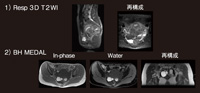

まず,MEDAL法によってin-phaseとout-of-phaseを撮像し,得られたデータから脂肪画像と水画像を算出した。MEDALはVolume撮像であり,われわれは現在,肝臓から骨盤までを2〜3回の呼吸停止下で撮像している。ただし,In- phase画像ではコイルの不均一性により,脂肪を均一な高信号域として描出できない。そこで,水画像を使用し,低信号な部分を計測すると,CT像とかなり良い相関が得られるようになり,しかも,20秒程度の短い息止め時間でデータが収集できた。図5は,MEDALからの計算画像での肝脂肪量の測定であり,MR spectroscopyを加えることで,さらに定量性に優れた評価が可能になる。

図5

図5 MEDAL:Fat fraction 計算画像:

SI(Fat image)/SI(In-phase)